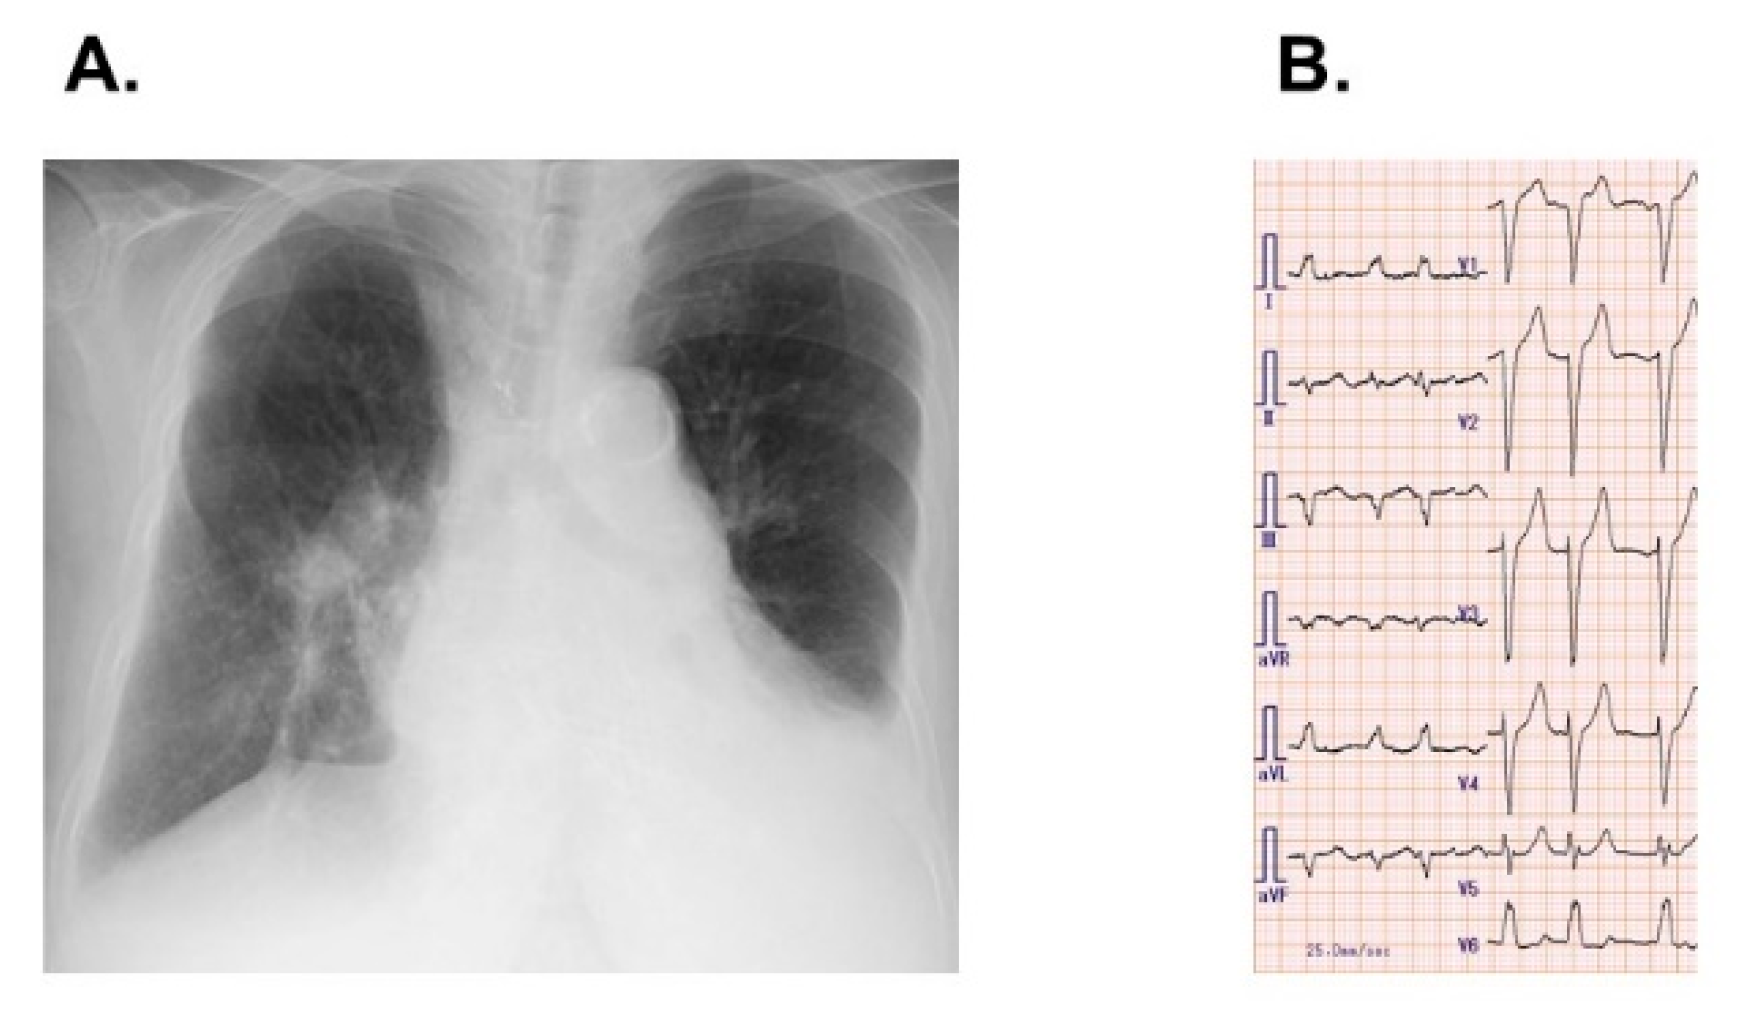

2. Case Report

2.1. On Admission